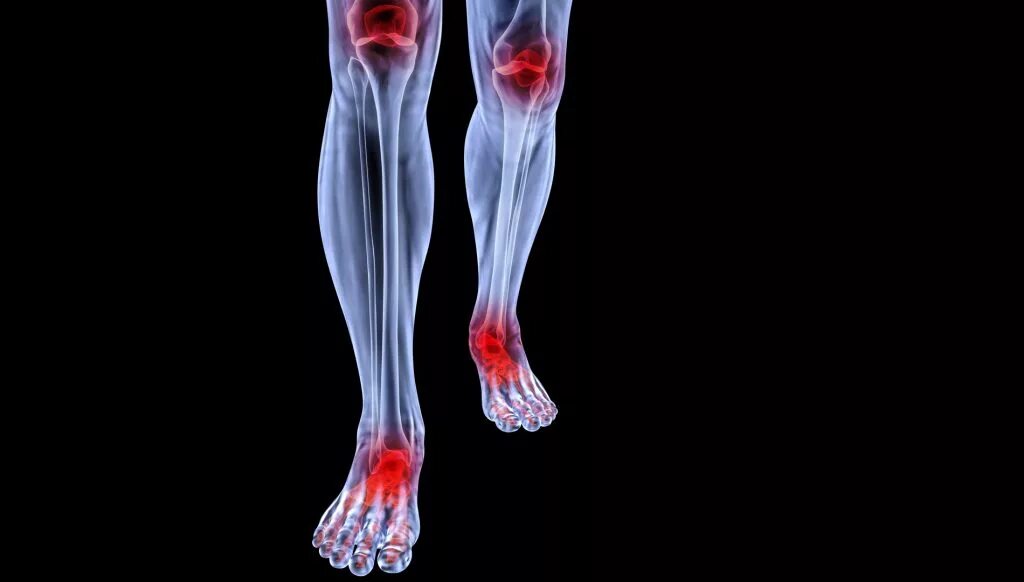

Ревматизм ног